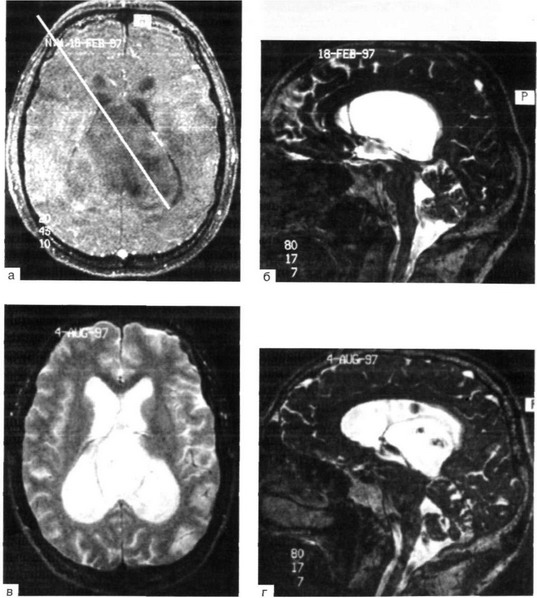

Рис. 38-8. Гигантская киста межжелудочковой перегородки.

Вверху: аксиальный (а) и сагиттальный (б) МРТ-срезы (фазово-контрастное исследование). Показана траектория продвижения эндоскопом сквозь передний рог правого бокового желудочка и просвет кисты в задний рог левого бокового желудочка; внизу: исследование через 6 мес после операции. Видна релаксация стенок кисты (в), появился просвет желудочков, которые до операции были практически полностью выполнены объемом кистознои мальформации. Темные области площади кисты на сагиттальном срезе (г) соответствуют окнам в ее стенках, прорезанным во время операции, и обусловлены турбулирующим током ликвора сквозь эти отверстия.